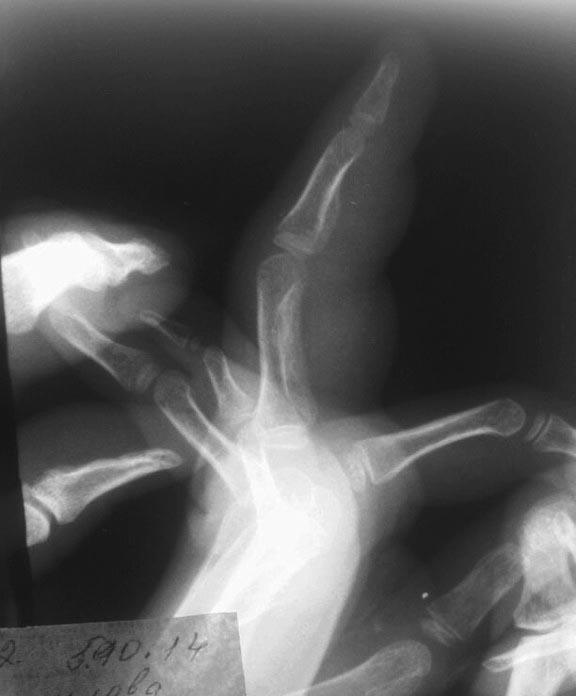

первый снимок через месяц после травмы.

второй снимок через 2 месяца после травмы. И снимок через 5 месяцев прямая проекция. Боковая проекция через 5 мес указана в самом начале